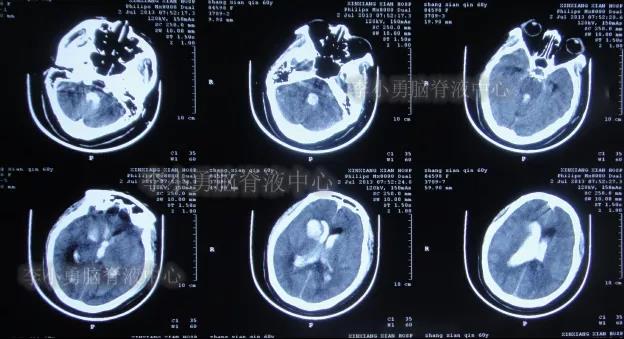

患者于2013年7月2日晨起,昏迷,意识不清,送入当地的河南省新乡县某医院,查头部CT示脑出血破入脑室(图-1)。

图-1:2013年7月2日头部CT脑出血